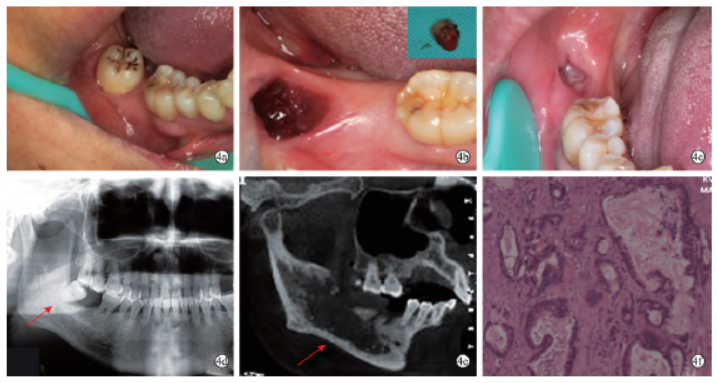

14例患者中有1名肝腺癌转移患者拔牙前及拔牙后4个月的CT特征发生了较大的骨质破坏变化(图3),因此本文取该病例拔牙后CT特征纳入统计。

图3 1例MAJ患者拔牙前后口内照、CT及病理切片(苏木精-伊红染色,×40)。3a:拔牙前口内照示48冠周牙龈红肿;3b:48拔除术后创口及患牙;3c:拔牙后4个月示48拔牙创仍未愈合;3d:拔牙前全景片示48阻生,根尖及牙周骨质吸收;3e:拔牙后4个月CBCT矢状位示溶骨型破坏边缘呈浸润型改变;3f:术中切除右下颌骨切片示致密的纤维组织背景下大量腺管样癌细胞浸润